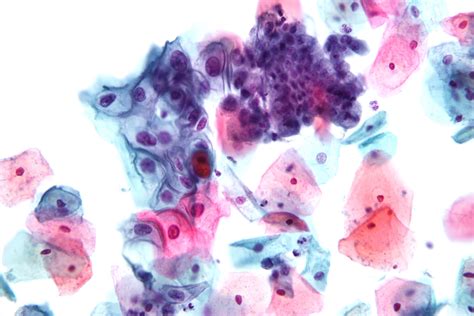

Taking a smear with the Szalay Cyto-Spatula Pap test ...

Taking a smear with the Szalay Cyto-Spatula Pap test ... from i.ytimg.com